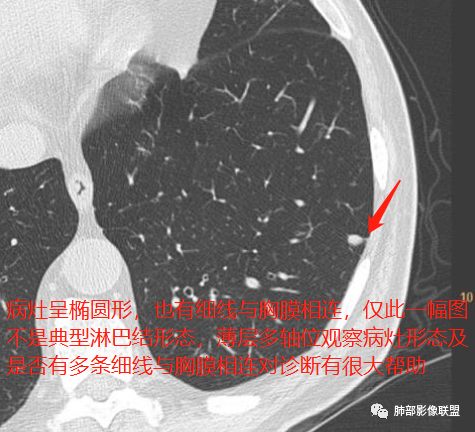

2、病灶边缘多平直,大部分呈三角形,部分呈椭圆形;

3、病灶边缘见一条或数条细线与胸膜相连。

长径均小于12mm。典型的形状为三角形,也可以为梭形、圆形或椭圆形。诊断的关键在于见到1-5条细线与胸膜、叶间胸膜或静脉相连,有时状如坐落于电路板的“二极管”,但以薄层CT显示为佳。有作者病理对照线状影为小叶间隔,有作者病理对照为淋巴管。其实不矛盾,因为淋巴管走行于小叶间隔内。

对怀疑肺内淋巴结的病例,必须行薄层扫描,推荐1.5mm及以下层厚。因为在5mm层厚图像,肺内淋巴结可以由于部分容积效应表现为磨玻璃密度结节,而且对线状影及病变形状的显示也欠清晰。

诊断肺内淋巴结最关键指出在于薄层扫描见到细线状影与胸膜、叶间胸膜及肺静脉相连。